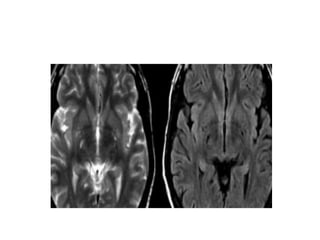

• One of the most common questions

in daily radiology practice when we

see an image like the one on the

left is:

• 'Do we have to think of Multiple

Sclerosis?

• Or are these white matter lesions

the result of small vessel disease, as

in a hypertensive patient?

• Or should we think of more

uncommon diseases?

• In order to be able to answer that

question, we have to realise that

when we study white matter lesions

(WMLs):

• Many neurological diseases can

mimic MS both clinically and

radiologically.

• Most incidentally found WMLs will

have a vascular origin.

• MS has a typical distribution of WMLs.

This can be very helpful in differentiating them from

vascular lesions .

Typical for MS

• involvement of corpus callosum,

• U-fibers,

• temporal lobes,

• brainstem,

• cerebellum

• spinal cord.

This pattern of involvement is uncommon in other

diseases.

In small vessel disease there may be involvement of the

brainstem, but it is usually symmetrical and central, while

in MS it is periphera

• The lesions in the deep white

matter (yellow arrow) are

nonspecific and can be seen in

many diseases.

Typical for MS in this case is:

• Involvement of the temporal

lobe (red arrow)

• Juxtacortical lesions (green

arrow) - touching the cortex

• Involvement of the corpus

callosum (blue arrow)

• Periventricular lesions -

touching the ventricles